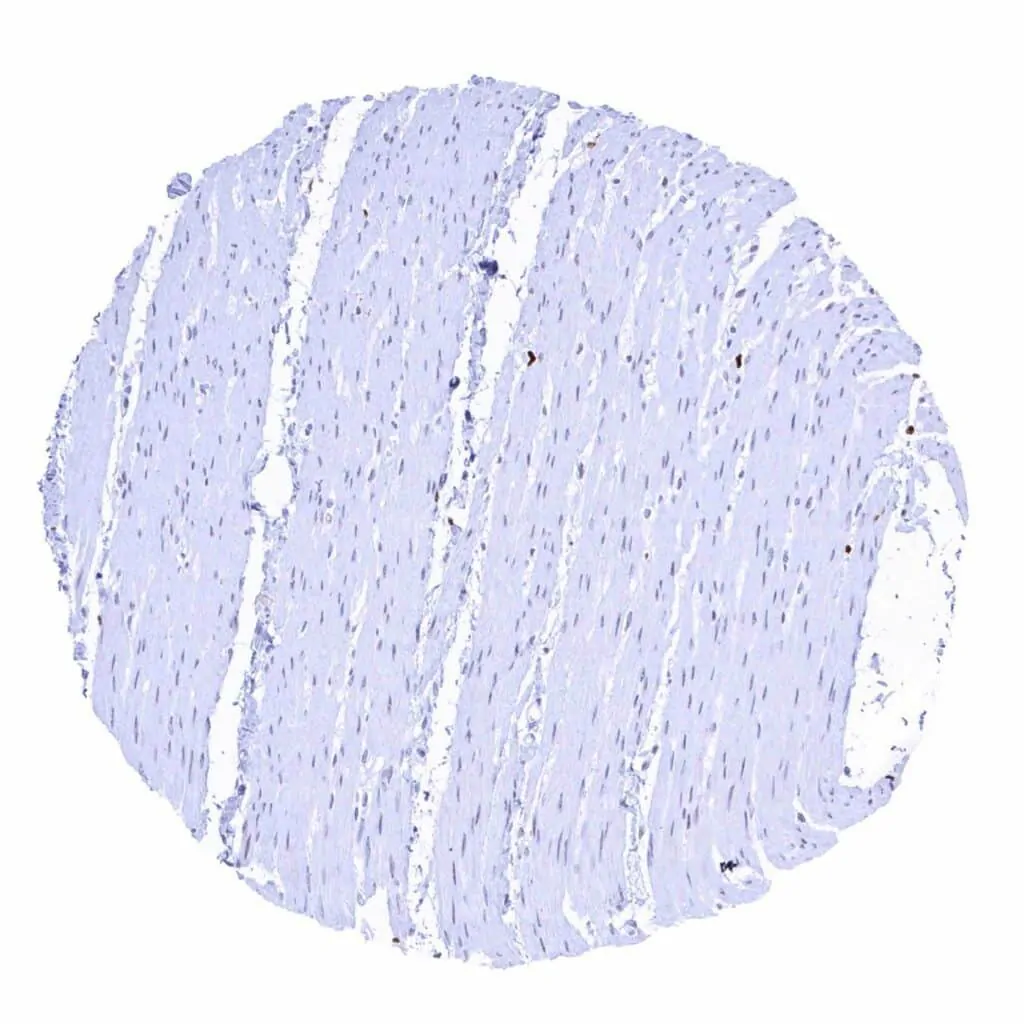

Aorta, media

Heart muscle – Faint MCM2 staining in some muscle cells